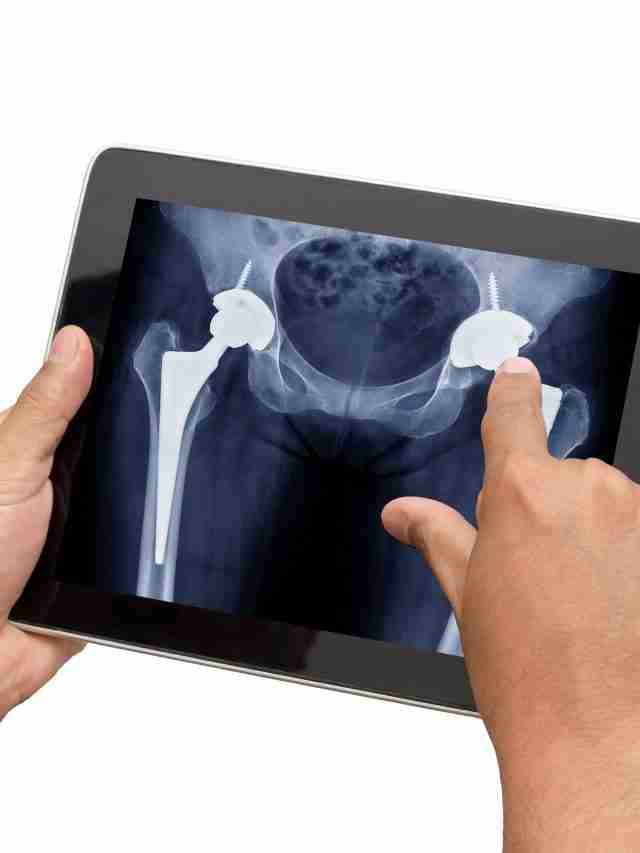

Hip replacements provide the ability to reduce severe pain and stiffness while improving function in over 400,000 people in the United States each year. There are different approaches your surgeon may take when replacing the hip joint. Read further to learn some tips and tricks to follow to ensure you have a speedy and healthy recovery.

There are a few differences in the beginning stages of recovery depending on the approach. Depending on your body shape, size, and status of your hip, your surgeon may approach the hip from posterior (the back side) or anterior (the front side).